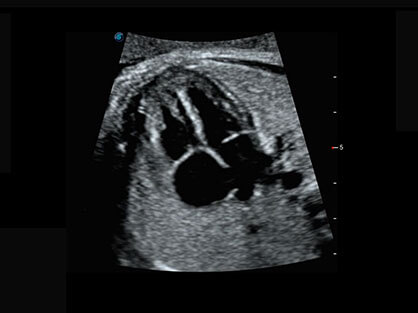

大角度腔内容积探头,可完整包络子宫及盆底结构,充分展示组织结构毗邻关系。